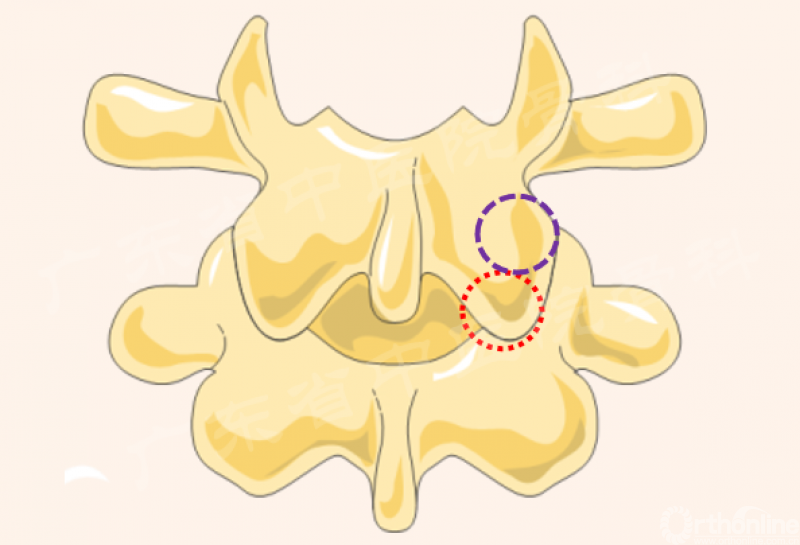

第3半管:半齿环锯-上关节突(尖及内侧)

关键:

尖部

外套管保护

骨凿OR枪咬上关节突

椎弓根内侧缘

神经根外缘

黄韧带止点(如有)